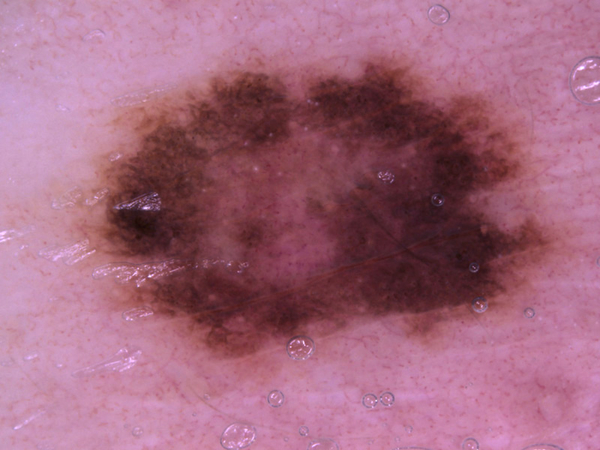

Testing Model: Skin Cancer

Classifies skin cancers (Always consult a medical professional)

Trained on: 10,015 images

Try a sample image (drag it into the box):

Actinic keratoses

Basal cell carcinoma

Benign keratosis-like lesions

Dermatofibroma

Melanoma

Melanocytic nevi

Vascular lesions